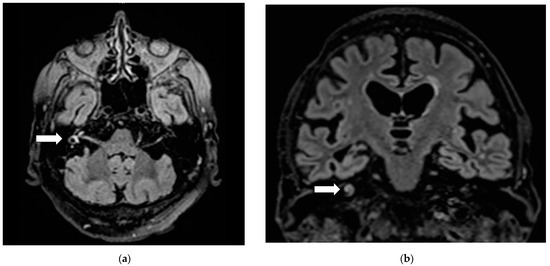

Brain magnetic resonance imaging excluded neurovascular neoplastic disease. However, vestibule, semicircular canals and cochlear on the right appeared hyperintense on FLAIR images (Figure 1) and on diffusion-weighted images, leading to the diagnosis of right labyrinthitis.

Figure 1.

Right labyrinthitis: Hyperintensity (arrows) on axial (a) and frontal (b) FLAIR sections in right vestibule, semicircular canals and cochlear.